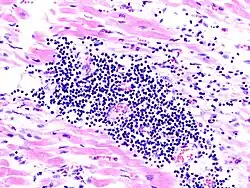

Die Koronarangiografie wird bei Patienten, welche sich als akutes Koronarsyndrom präsentieren, zum Ausschluss einer koronaren Herzkrankheit notfallmäßig durchgeführt. Sie ist ebenfalls bei Patienten mit einer deutlich erniedrigten linksventrikulären Pumpfunktion indiziert und für die Durchführung einer Myokardbiopsie notwendig. Die Myokardbiopsie ist der Goldstandard bei der Diagnostik der Myokarditis. Denn nur durch eine Myokardbiopsie kann die Ursache für eine Myokarditis gesichert und eine entsprechende, personalisierte Therapie eingeleitet werden. Dies bedeutet natürlich, dass die Myokardbiopsie auf möglichst alle möglichen Ursachen einer Myokarditis untersucht werden sollte. Hierzu gehört eine histologische (Wie sieht das Gewebe aus?), immunhistologische (Welche Zellen sind beteiligt? Gibt es Anzeichen für eine autoimmune Genese?) und molekularbiologische (z. B. PCR-Methoden zur Analyse, welche Viren beteiligt sind) Untersuchung der Myokardbiopsie. Neuerdings werden zudem microRNAs und Gen-Expressions-Profile zur Diagnostik eingesetzt.